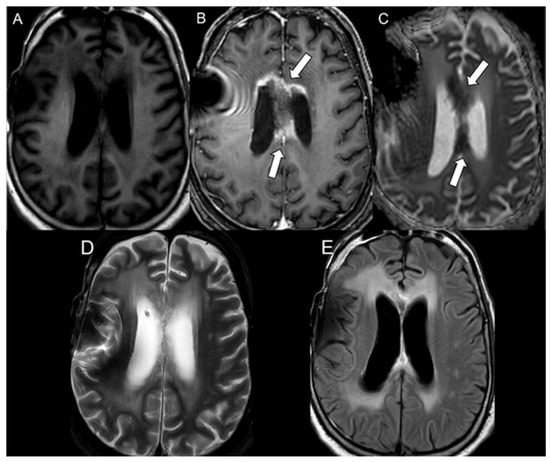

| Bevacizumab | 21 | 248.1 ± 67.2 | 647.2 ± 94.6 | <0.001 |

| Progressive glioblastoma | 49 | 752.8 ± 132.5 | 709.2 ± 63.5 | 0.08 |

| Radiation necrosis | 58 | 479.0 ± 105.2 | 723.3 ± 64.0 | <0.001 |

| Bevacizumab | 21 | 0.39 ± 0.10 |

| Progressive glioblastoma | 49 | 1.07 ± 0.22 |

| Radiation necrosis | 58 | 0.66 ± 0.14 |